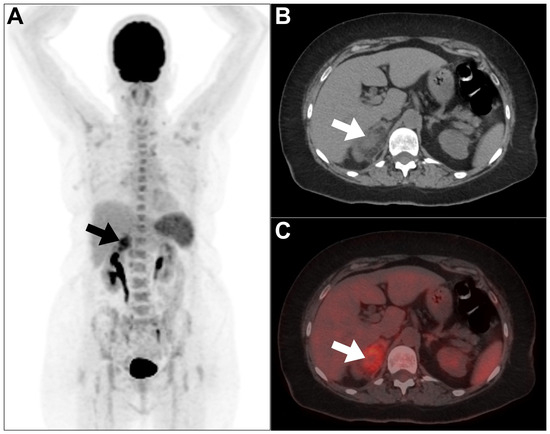

- Xu, Z.; Cai, T.; Zhang, X.; Wu, J.; Liu, C. Xanthogranulomatous pyelonephritis infected with the Providencia stuartii: A case report and literature review. BMC Nephrol. 2021, 22, 356. [Google Scholar] [CrossRef] [PubMed]

- Joshi, P.; Lele, V.; Shah, H. Fluorodeoxyglucose positron emission tomography-computed tomography findings in a case of xanthogranulomatous pyelonephritis. Indian J. Nucl. Med. 2013, 28, 49–50. [Google Scholar] [CrossRef] [PubMed]

- Liu, Y.; Tong, G.; Wen, Z. Focal Xanthogranulomatous Pyelonephritis on FDG PET/CT. Clin. Nucl. Med. 2022, 47, e611–e612. [Google Scholar] [CrossRef]

- Swingle, C.A.; DBaumgarten, A.; Schuster, D.M. Xanthogranulomatous pyelonephritis characterized on PET/CT. Clin. Nucl. Med. 2005, 30, 728–729. [Google Scholar] [CrossRef]